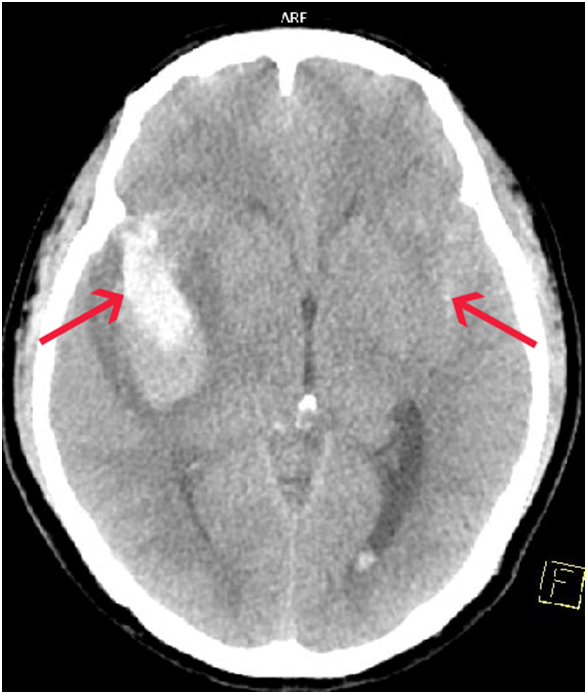

當腦動脈瘤滲漏或破裂,血液會溢出大腦表面(蜘蛛膜下腔),患者會感到爆裂性頭痛;其他症狀包括噁心和嘔吐、頸部僵硬、畏光、精神錯亂、虛弱和喪失意識。嚴重SAH更會導致血管痙攣令大腦供氧減少,或血液在大腦周圍積聚而造成腦積水。

腦動脈瘤一旦出現滲漏或破裂須進行緊急手術,要盡快通過手術夾閉或堵塞腦動脈瘤以防止再出血或擴大(請參閱以下圖表)。如腦內血塊壓迫腦部影響供血,應即時進行手術移除血塊,並考慮放置支架引流腦積水及減低腦壓。然而,考慮到某些特殊情況,例如病人處於昏迷狀態、本身有嚴重疾病、高齡等,一般要等到病情穩定才安排治療。

(特此致謝聖德肋撒醫院掃描部提供醫學影像圖片)